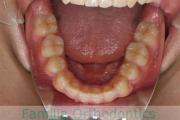

No.23V-061

- 主な症状:

- 叢生

- その他の症状:

- 上下顎前突

- 年齢:

- 23歳

- 性別:

- 女性

- 抜歯部位

- 上:

- 44

- 下:

- 主な使用装置:

- FEA 022

- 治療にかかった費用:

- 88万円

でこぼこを綺麗に並べたいということで来院されました。上下左右から小臼歯を抜歯して、マルチブラケット法を2年半、30回程度通院していただいて行いました。

かなり強い叢生(でこぼこ、凹凸、ガタガタ)のため、保定をしっかりしないと後戻りのリスクが高いケースといえます。

- ≫治療前

-

上顎

下顎

前歯の関係など

右側

正面

左側